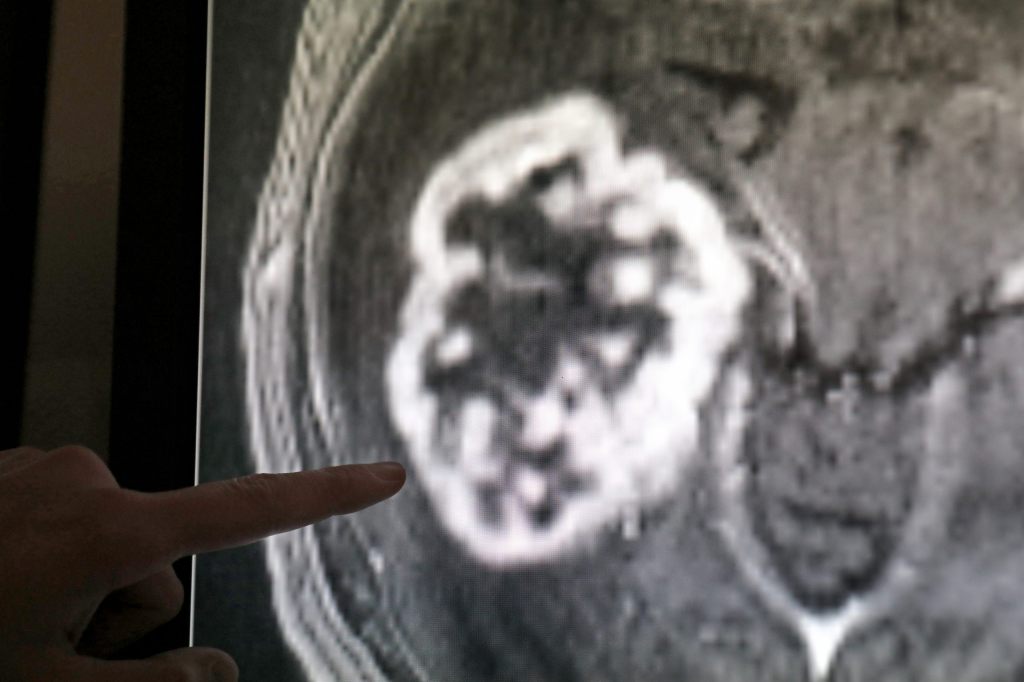

Anstieg um 80 Prozent: Immer mehr junge Menschen haben Krebs

Dies geht aus einer gross angelegten Studie hervor, die am Mittwoch veröffentlicht wurde. Die Zahl der weltweiten Fälle von Krebs in der Altersgruppe der 14- bis 49-Jährigen ist von 1,82 Millionen im Jahr 1990 auf 3,26 Millionen im Jahr 2019 gestiegen, wie die Studie im Fachblatt «BMJ Oncology» zeigt.

Auch die Zahl der Todesfälle in Folge einer Krebserkrankung ist bei den unter 50-Jährigen laut der Studie stark angestiegen. Im Jahr 2019 starben mehr als eine Million Menschen unter 50 an Krebs, das waren rund 28 Prozent mehr als im Jahr 1990. Die tödlichsten Krebserkrankungen waren Brust-, Luftröhren-, Lungen-, Darm- und Magenkrebs. Den stärksten Anstieg beobachteten die Forscherinnen und Forscher bei Luftröhren- und Prostatakrebs. Die Fälle von Leberkrebs gingen hingegen zurück.